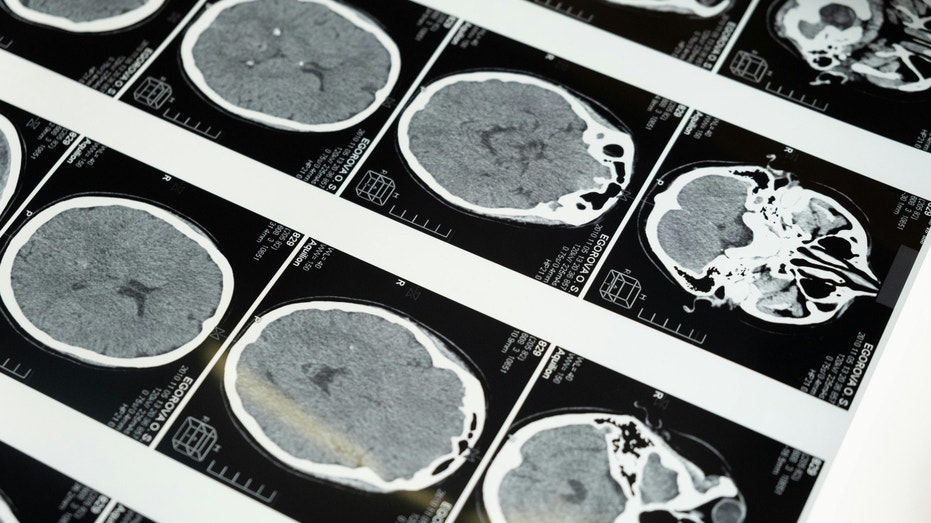

China’s ultrasound brain tech race heats up

Chinese company Gestala develops non-invasive ultrasound brain-computer interfaces as alternative to surgical implants, targeting chronic pain treatment.